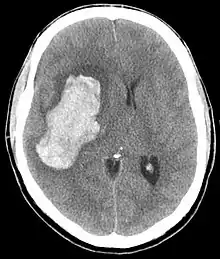

CT scan depicting intracranial hemorrhage, a possible complication of hypertensive emergency. Patients with spontaneous intracranial hemorrhage present with newfound headache and neurologic deficits.

In the brain, hypertensive encephalopathy - characterized by hypertension, altered mental status, and swelling of the optic disc - is a manifestation of the dysfunction of cerebral autoregulation. Cerebral autoregulation is the ability of the blood vessels in the brain to maintain a constant blood flow. People with chronic hypertension can tolerate higher arterial pressure before their autoregulation system is disrupted. Hypertensives also have an increased cerebrovascular resistance which puts them at greater risk of developing cerebral ischemia if the blood flow decreases into a normotensive range. On the other hand, sudden or rapid rises in blood pressure may cause hyperperfusion and increased cerebral blood flow, causing increased intracranial pressure and cerebral edema, with increased risk of intracranial bleeding.[6]